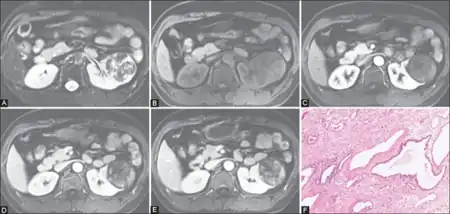

a-e)MRI shows a complex but predominantly solid heterogeneous left renal mass, f) photomicrograph

Diagnosis of mesoblastic nephroma and its particular type (i.e. classic, mixed, or cellular) is made by histological examination of tissues obtained at surgery. Besides its histological appearance, various features of this disease aid in making a differential diagnosis that distinguish it from the following childhood neoplasms: